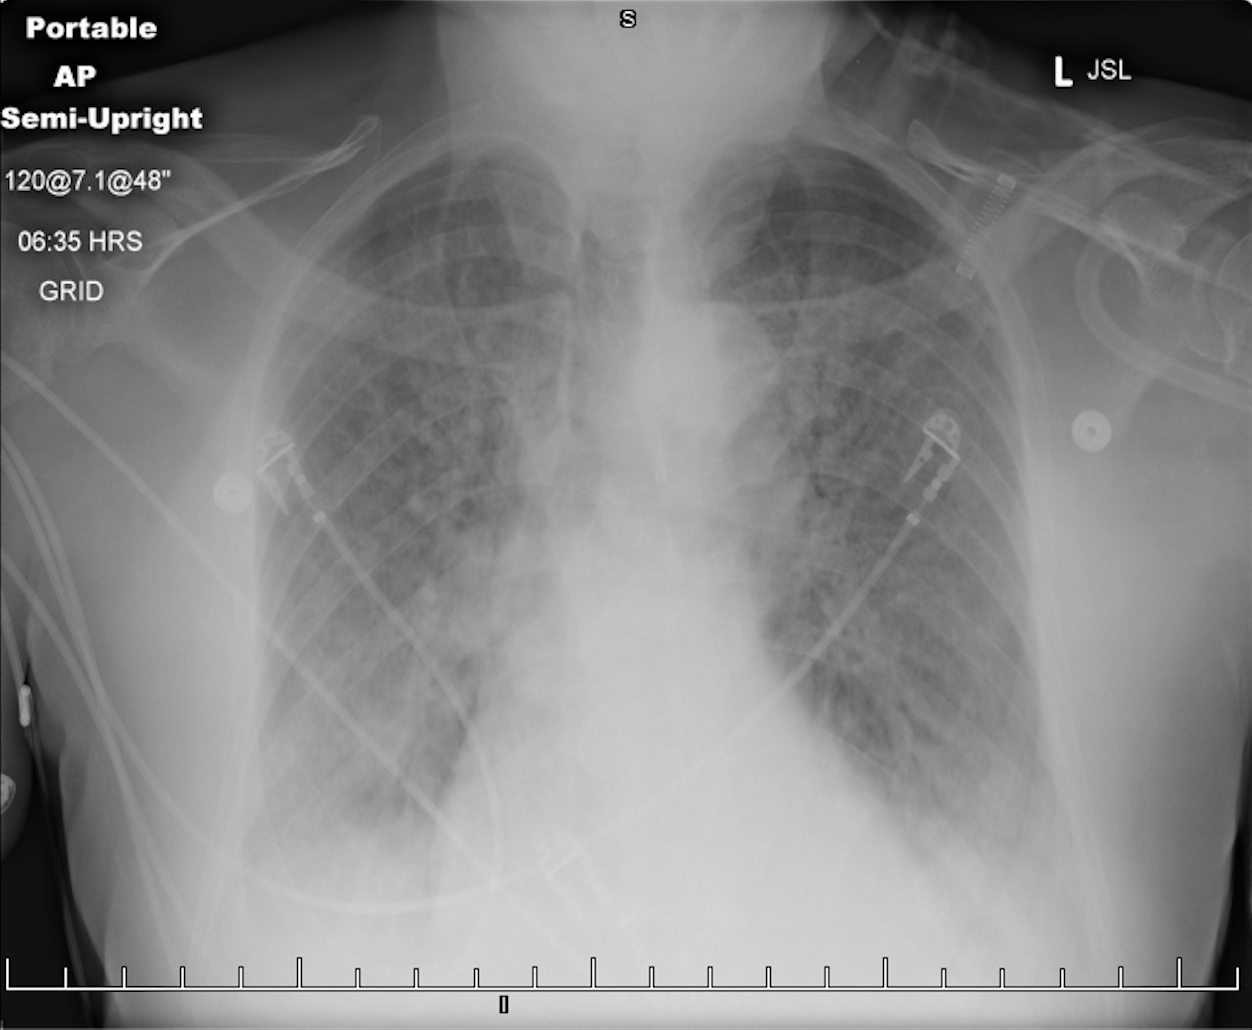

A 77-year-old woman presented to the emergency department with shortness of breath. She had a medical history significant for COPD, CAD, myocardial infarction status after coronary artery bypass grafting,...

01/28/2023